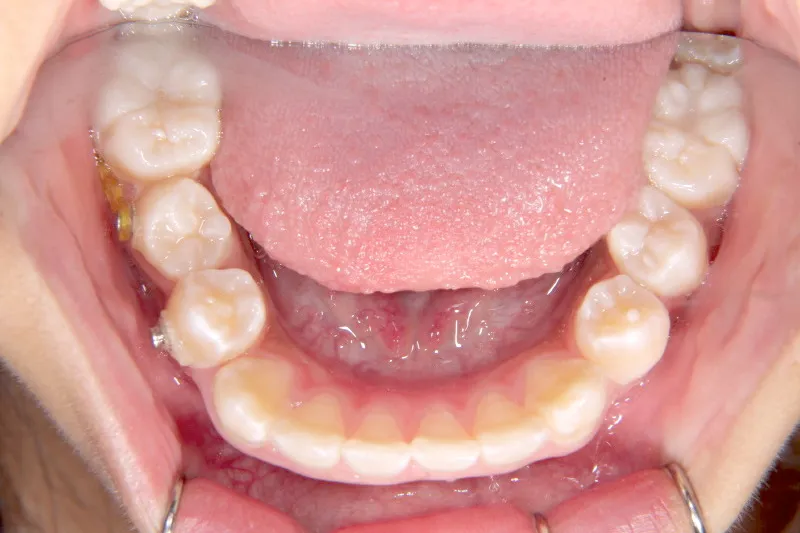

【子供の矯正(一期)】叢生・開咬・前歯で噛めない・舌癖・7歳女児【M.O様】

治療終了後

治療回数31回、4年11ヶ月の治療期間で矯正治療を終了しました。

主訴が改善され、ご満足頂きました。